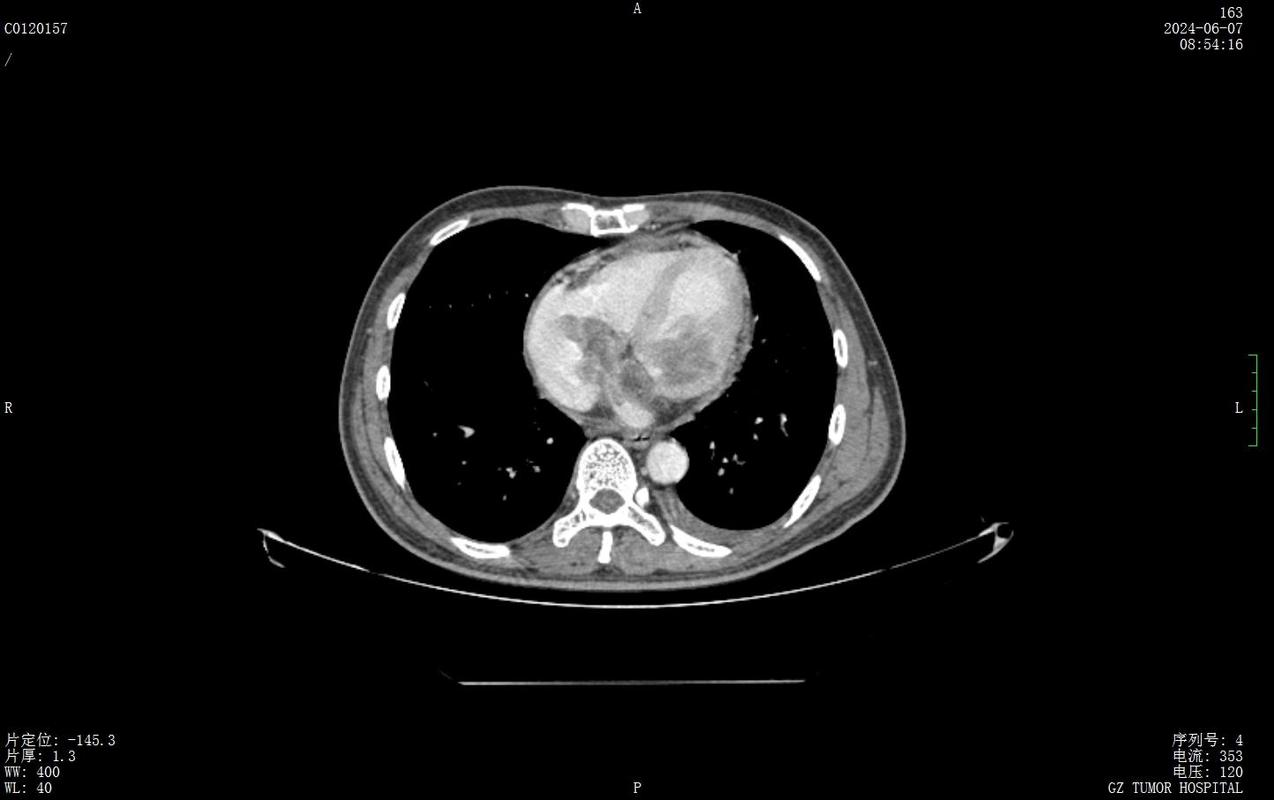

心梗后室壁瘤

图片尺寸2988x5312